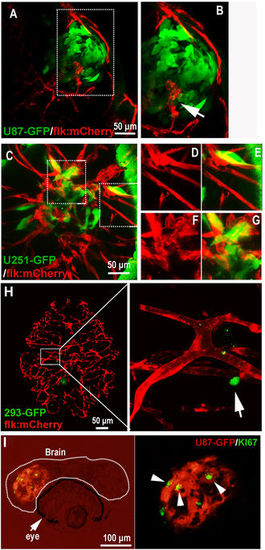

Establishment of GBM xenografts in flk:eGFP Casper zebrafish. (A,B) 200?500 GBM tumor cells (U87-RFP, U251-RFP) were intracranial implanted into 3dpf flk:eGFP Casper zebrafish and monitored by confocal microscope every 24?hours, 293T-RFP cells implantation was set as control. Areas in dotted boxes were magnified right, arrows indicating infiltrating tumor cells. (B) The survivorship curve of U87 and U251 tumor-bearing zebrafish and control 293?T injected zebrafish. (C) A high-resolution image of intracranially implanted 293t-RFP cells at 6dpf, arrows indicating the cell debris. (D) A reconstructed 3D image of a U87-GFP xenograft in the deep brain of flk:mCherry zebrafish at 6dpf, arrows indicating infiltrating tumor cells. Z-stack serial images show the depth of the GBM xenograft in zebrafish brain, arrows indicating infiltrating tumor cells. |

Active interaction between GBM xenografts and cerebral capillaries. (A,B) U87-GFP xenografts induced angiogenesis from neighboring host vessel within the tumor xenograft at 5dpi, area in dotted box was magnified in B, and arrow indicating the endothelial sprouts. (C?G) Tumor induced angiogenesis (F,G) and infiltrative tumor growth (D,E) of U251-GFP xenografts at 5dpi were detected in the zebrafish brain. (H) Representative image showing the 5dpi zebrafish brain with 293-GFP cells (arrow)(200?500 293-GFP cells were implanted into the brain of 3dpf zebrafish); implanted 293-GFP cells failed to survive in the brain parenchyma and cerebral capillaries were not affected by 293-GFP cells. (I) Immunostaining of U87 xenograft in zebrafish brain indicating the implanted tumor cells were proliferating (ki67+), arrowheads indicating the GFP+/ki67+ tumor cells in the xenograft in zebrafish. EXPRESSION / LABELING: